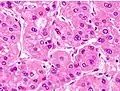

Micrograph of hepatocellular carcinoma. Liver biopsy. Trichrome stain.

Macroscopically, liver cancer appears as a nodular or infiltrative tumor. The nodular type may be solitary (large mass) or multiple (when developed as a complication of cirrhosis). Tumor nodules are round to oval, gray or green (if the tumor produces bile), well circumscribed but not encapsulated. The diffuse type is poorly circumscribed and infiltrates the portal veins, or the hepatic veins (rarely).[17]

Microscopically, the four architectural and cytological types (patterns) of hepatocellular carcinoma are: fibrolamellar, pseudoglandular (adenoid), pleomorphic (giant cell), and clear cell. In well-differentiated forms, tumor cells resemble hepatocytes, form trabeculae, cords, and nests, and may contain bile pigment in the cytoplasm. In poorly differentiated forms, malignant epithelial cells are discohesive, pleomorphic, anaplastic, and giant. The tumor has a scant stroma and central necrosis because of the poor vascularization.[41] A fifth form – lymphoepithelioma like hepatocellular carcinoma – has also been described.[42][43]